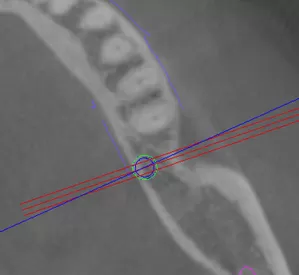

上記は左側が、ガイドを使用した場合の適切な位置、右側が、ガイドを使用しない場合に高確率で起こる不適な位置です。

本来入れるべき骨から逸脱している可能性があります。もちろん経験によってはここまで大きく外れることはありませんが、理論的には十分骨穿孔を起こす可能性があります。

上記は左側が適切にガイド使用した場合、右側がガイドをしない場合の比較です。